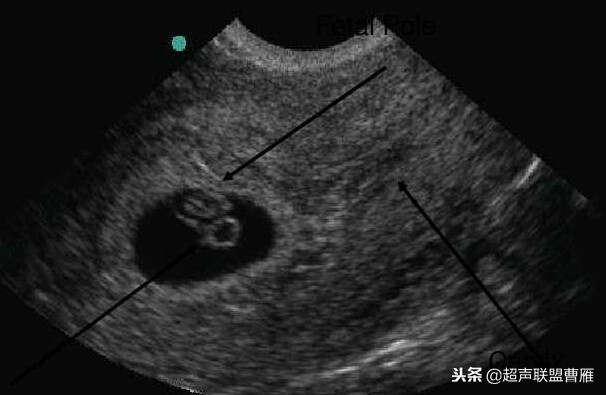

正常早孕卵黄囊声像图

早孕 胚芽 卵黄囊

5周+ 、6周+ 声像图

孕7周左右(胚芽11mm 卵黄囊)

宫内早孕 (7周左右)

正常宫内胚胎组织、卵黄囊